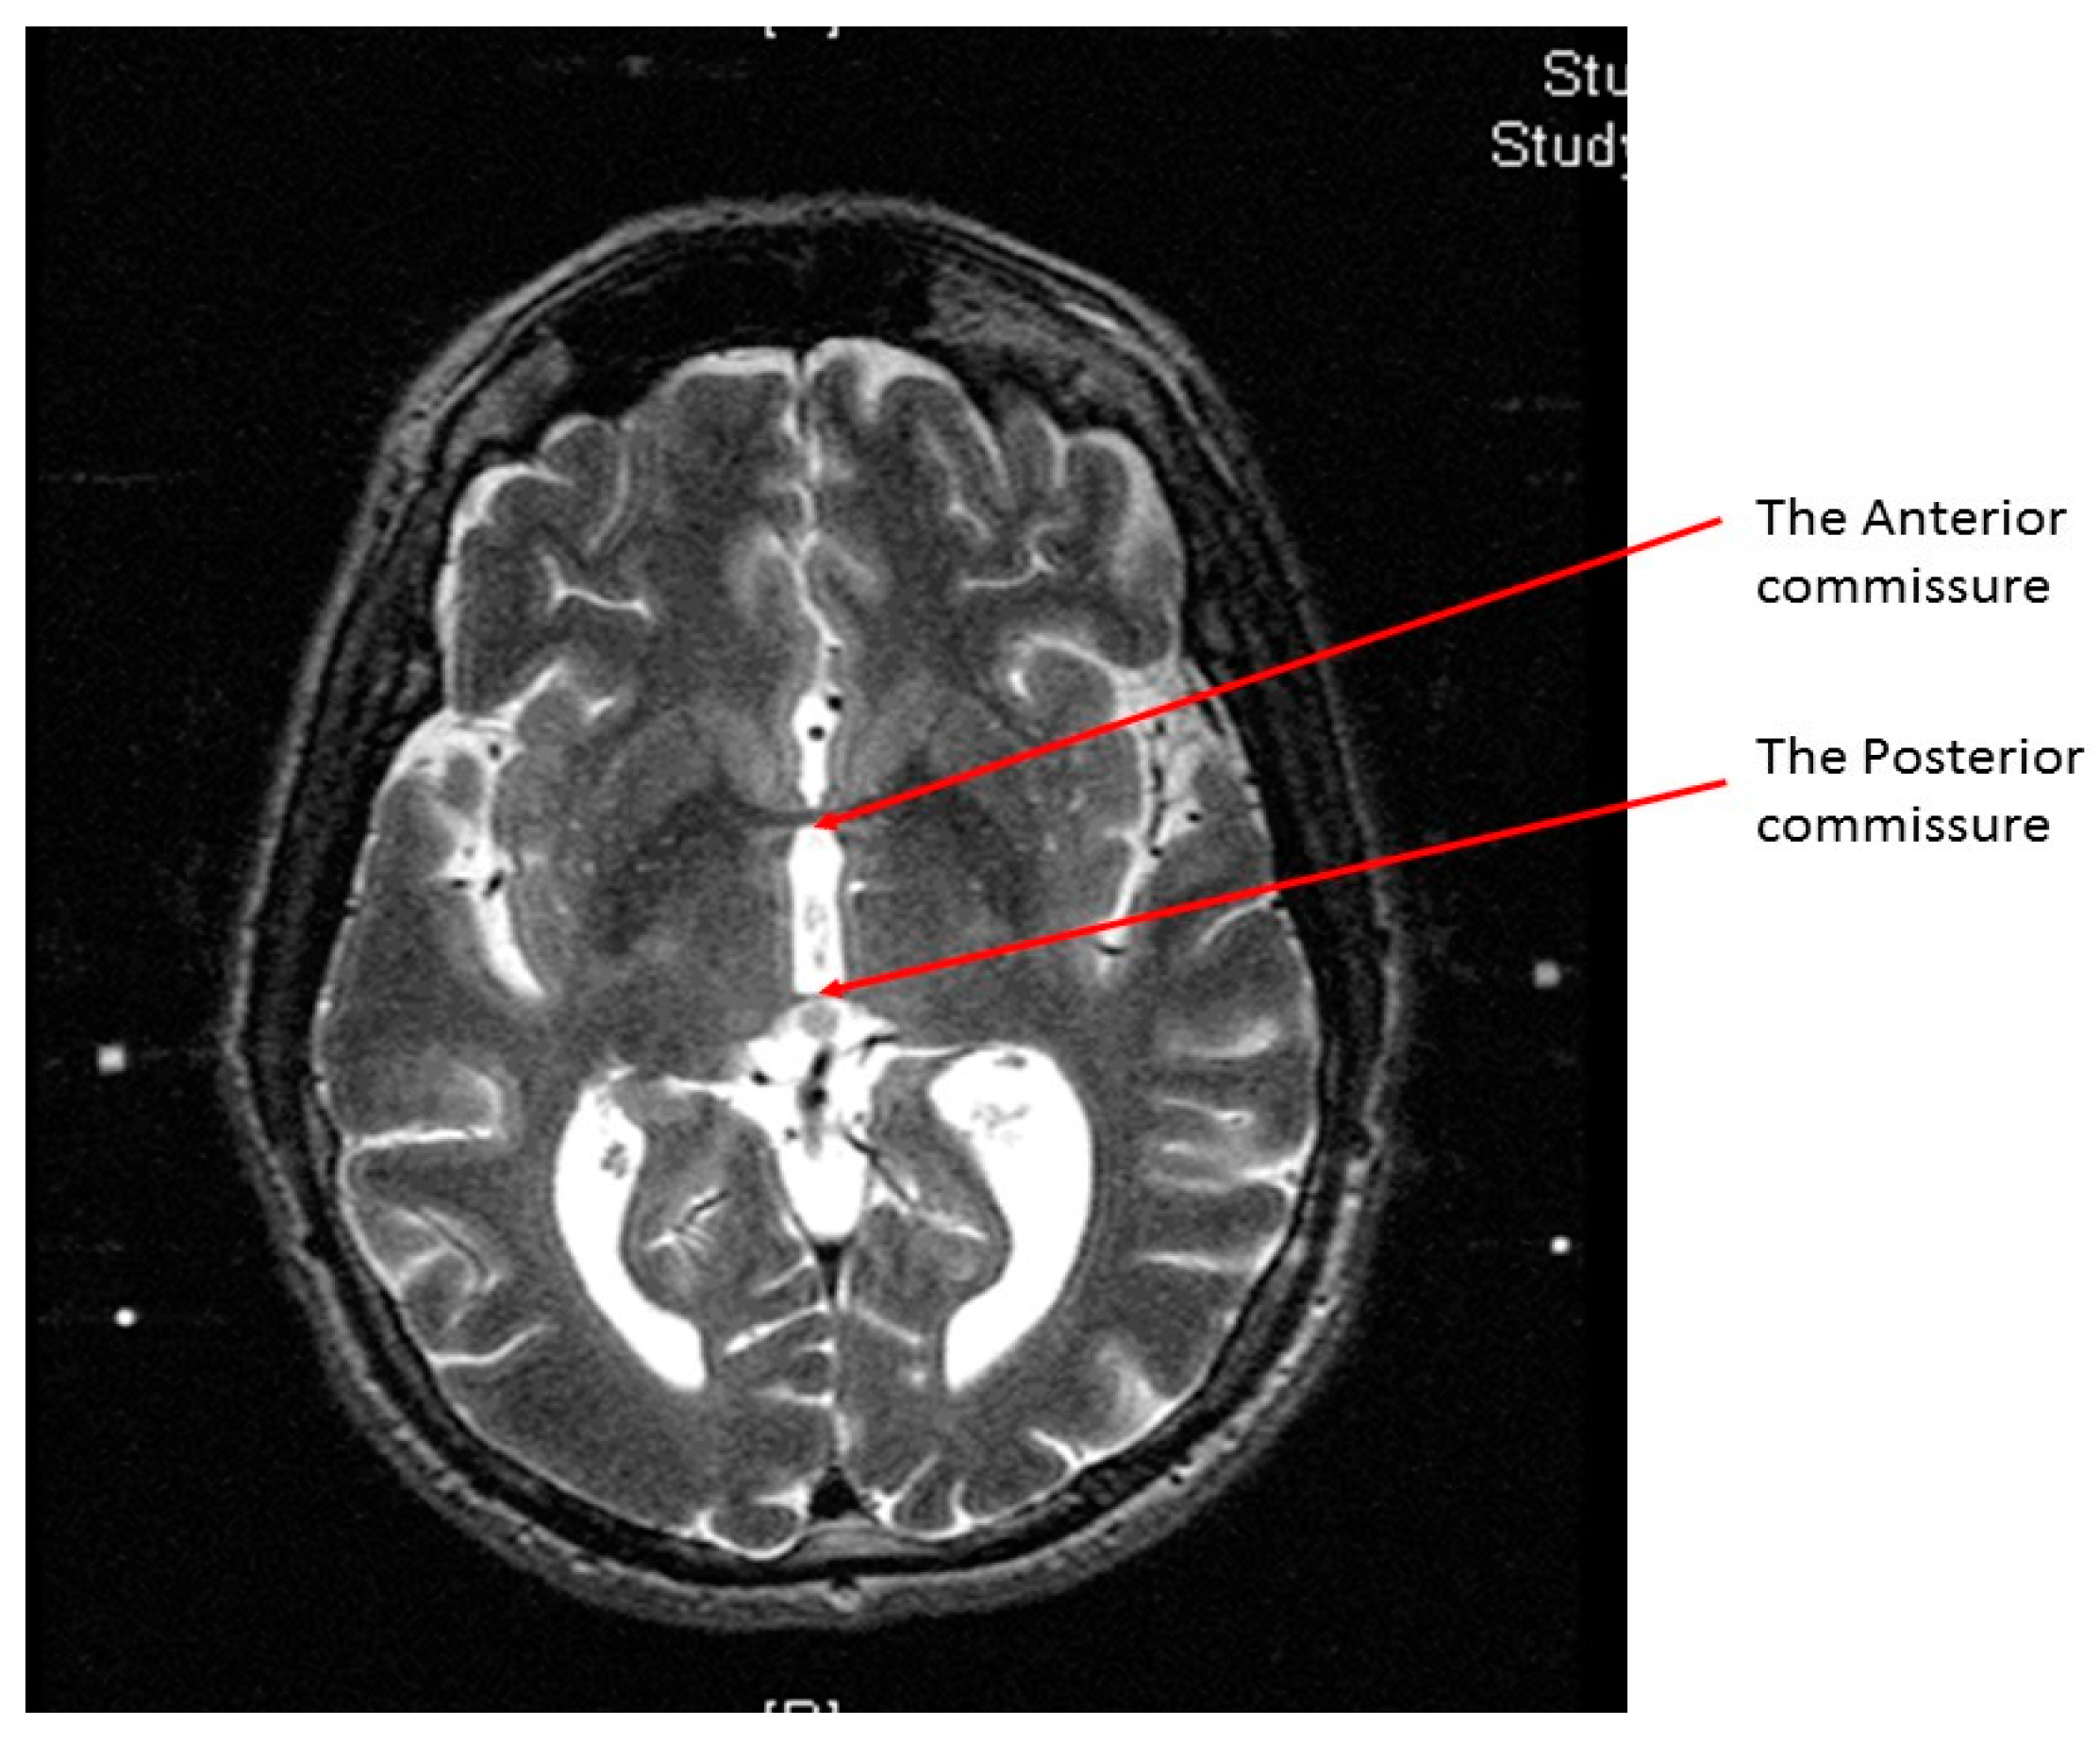

At the end of the scan, we chose the axial T2 image (or two adjacent images) in which the anterior commissure (AC) and the posterior commissure (PC) are identified (Figure 2). Then, we measured the distance between the middle and lower fiducials on both sides of the frame, and a maximum of 2 mm difference was allowed. The X and Y MR coordinate of the center of the frame was obtained at the point of meeting of two diagonal lines drawn on the MR console between the opposing anterior and posterior fiducials. After that, the X and Y MR coordinates of both the AC, the PC, and the center of the frame (Figure 3) were obtained from the MR console, and entered into a simple Excel worksheet (Microsoft, Redmond, WA, USA) designed by the senior author.

Figure 2.

An axial T2 weighted magnetic resonance image showing the anterior commissure and the posterior commissure at the same cut.